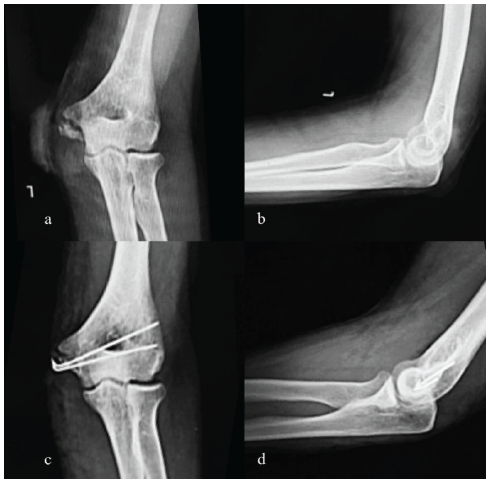

(K-wire) A 35-year-old male presented after injury by blades of a fan, with contused lacerated wound over elbow with pain, swelling, and restricted motion with a transected ulnar nerve. Radiographs showed a displaced, comminuted medial epicondyle fragment. He underwent open reduction and fixation with two smooth K-wires, along with ulnar nerve repair with graft. At 10 weeks, the wires were removed, and union was confirmed. Final ROM was 0–135°, with only mild scar tenderness reported (Fig. 4).

Figure 4: Pre-operative and post-operative X-rays left elbow (a) pre-operative X-ray left elbow anterior-posterior (AP) view, (b) pre-operative X-ray left elbow lateral view, (c) post-operative X-ray left elbow AP view, (d) post-operative X-ray left elbow lateral view.